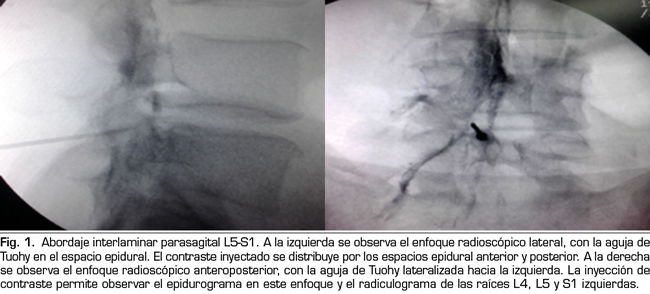

Resultados: Un total de 154 pacientes recibieron betametasona epidural. En 29 de ellos se realizó un abordaje interlaminar parasagital y en 25 transforaminal. La betametasona administrada por la vía interlaminar parasagital redujo la puntuación en la EVN un 20 %, y por la vía transforaminal en un 36 %. Estas diferencias fueron estadísticamente signifi cativas cuando se compararon los datos basales y los obtenidos al mes de los procedimientos (prueba t de Student para muestras pareadas), sin encontrarse diferencias estadísticamente significativas entre grupos (prueba t de Student para muestras independientes). Los Índices de Intensidad e Interferencia también fueron reducidos por la inyección epidural de esteroides, sin diferencias significativas entre ambos accesos. La frecuencia de respuestas satisfactorias fue mayor en el grupo tratado por vía transforaminal, 16/25 (64 %) frente a 11/29 (38 %) en el grupo tratado por vía interlaminar, diferencia estadísticamente significativa, con un valor de p = 0,01 (prueba de Chi cuadrado). En aquellos pacientes definidos como respondedores, la betametasona administrada por los dos abordajes produjo una reducción clínica y estadísticamente significativa del dolor y de su repercusión evaluados por el IAD, sin encontrarse diferencias significativas entre los abordajes.

Conclusión: La inyección de betametasona epidural administrada por vía interlaminar parasagital y transforaminal redujo la intensidad del dolor y su interferencia funcional en pacientes con dolor radicular crónico. Los abordajes interlaminar parasagital y transforaminal fueron similares en eficacia, aunque con una frecuencia de respuestas satisfactorias mayor en los pacientes tratados por vía transforaminal. La inyección interlaminar parasagital de esteroides es una alternativa válida a la vía transforaminal, sin sus riesgos neurológicos.